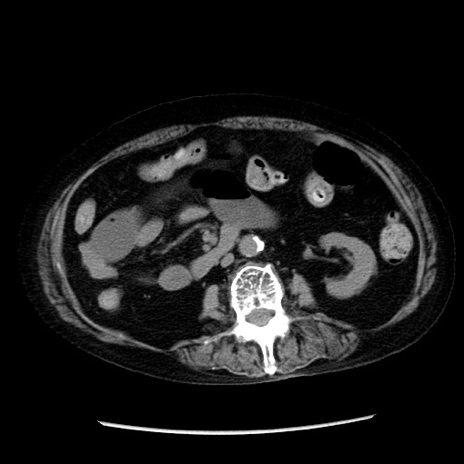

症例14(横断像)

冠状断像

【症例】 90歳代女性

【主訴】 腹痛・嘔吐

【現病歴】今朝から左側腹部痛を認めた。 経過観察していたが、嘔吐を認めたため来院。

【既往歴】 子宮癌術後

【身体所見】 意識清明、BP 127/54mmHg、P 98bpm Sp02 95%(RA)、BT 35.8°C、腹部平坦・軟腸ぜん動音聴取良好、右下腹部圧痛(+) 反跳痛なし

【データ】WBC 9800、CRP 0.46